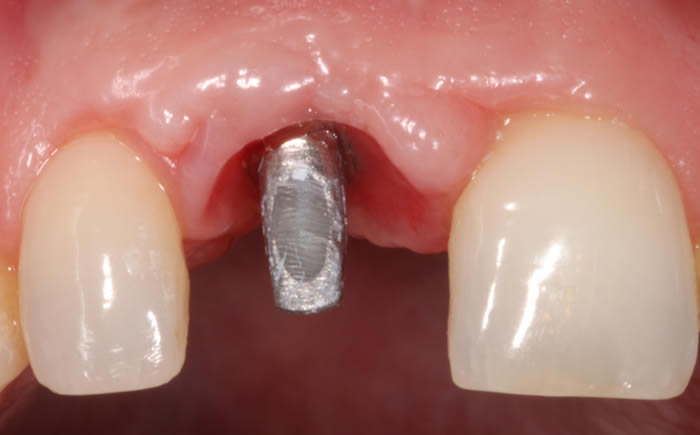

More front teeth replaced by dental implants

Case Three (4 images)